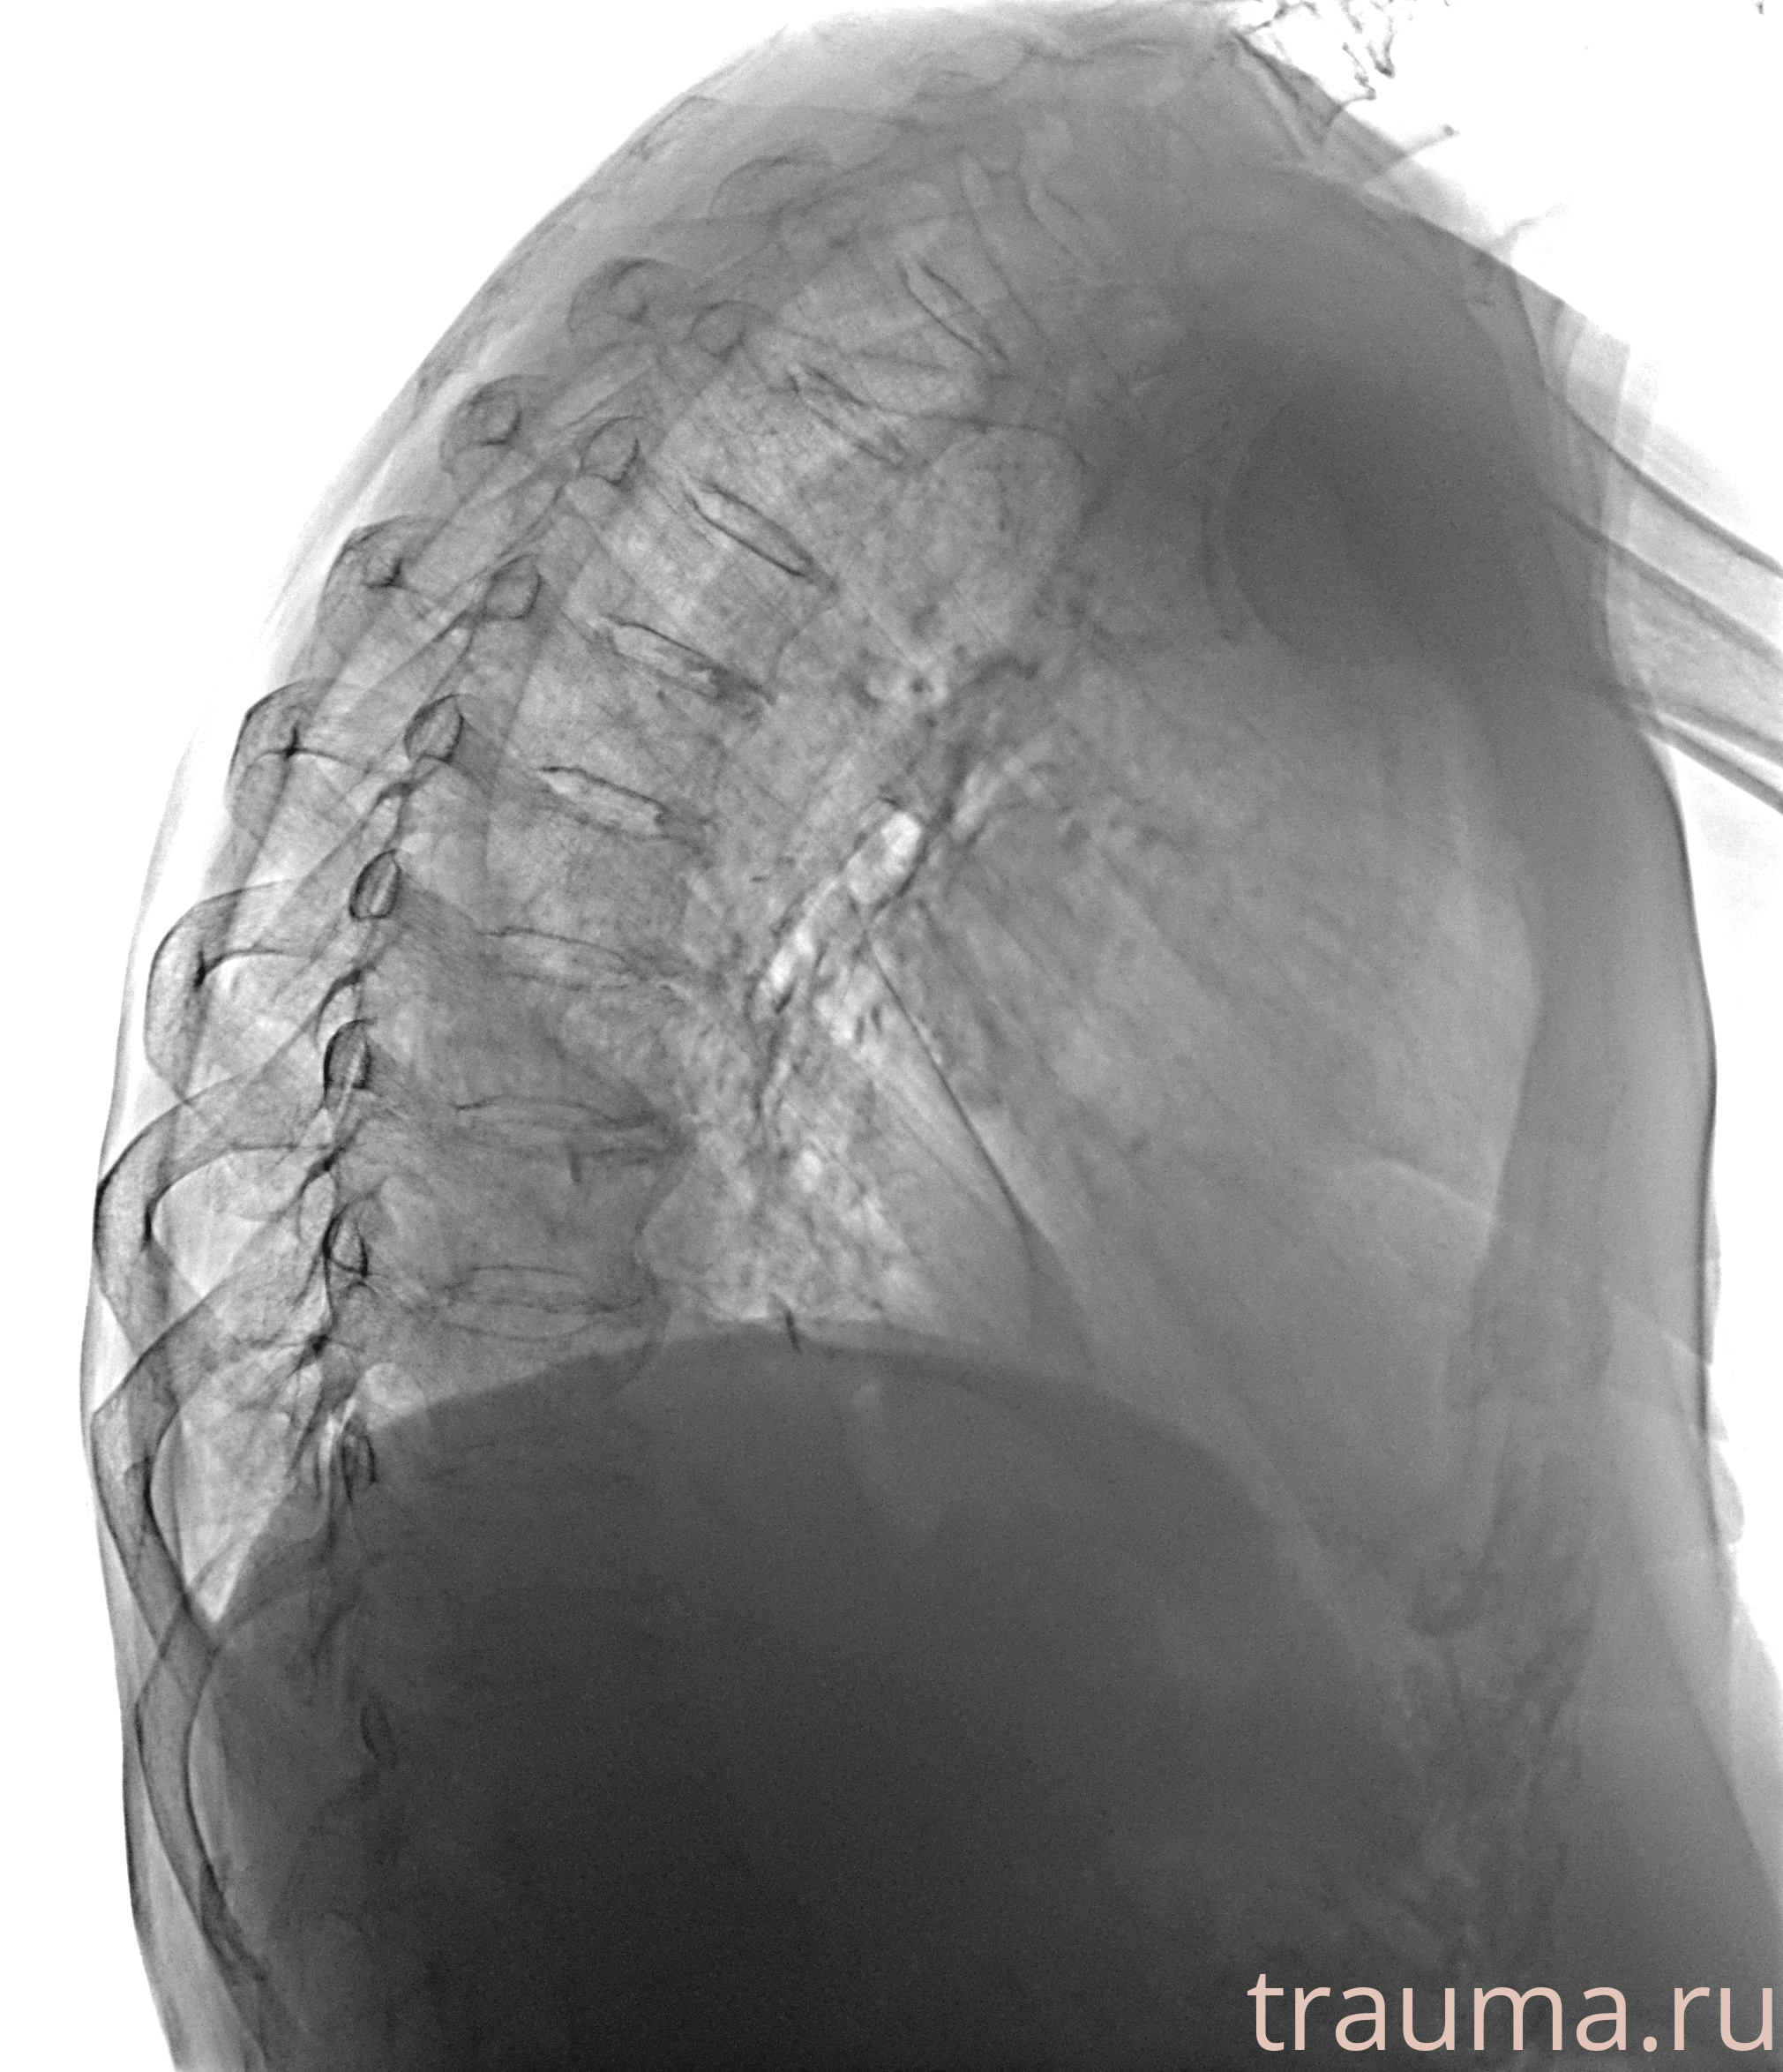

Рентгенограммы

Рентген на дому: по вашему адресу приезжает врач-рентгенолог, травматолог-ортопед с мобильным рентгеновским аппаратом, проводит диагностику травмы или заболевания, делает необходимые рентгенограммы, дает рекомендации по дальнейшему лечению. Получить качественные снимки в домашних условиях возможно благодаря уникальной методике, разработанной МосРентген Центром для института  Склифосовского